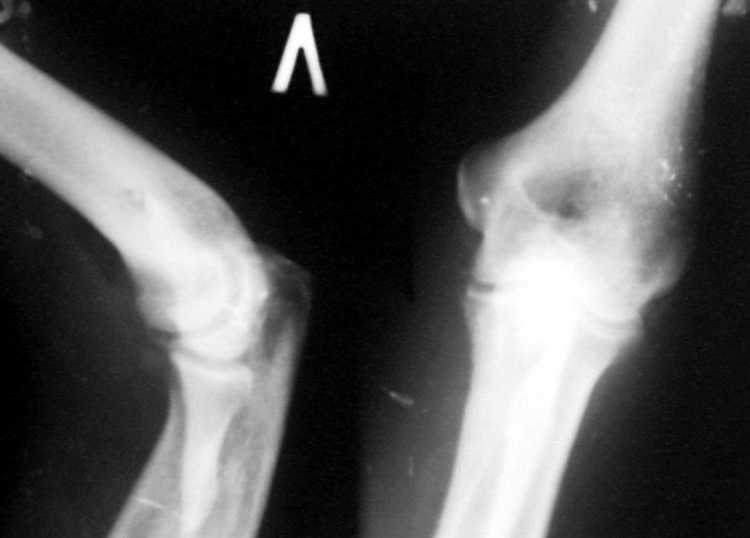

Поступил пациент, 47 лет. травма 15 сентября - вывих предплечья, репозиция. Фиксация 1 месяц.

До настоящего времени не обращался. Вот рентенограммы на 2-й и 3-й месяцы после травмы. Неврологии нет. Имеется контрактура локтевого сустава (сгибиние 90, разгибание 120). На снимках что-то похожее на гетеротопические оссификаты, такое впечатление. Как лучше восстановить функцию, возможно ли применить редрессацию? Все-таки локтевой сустав "капризный".